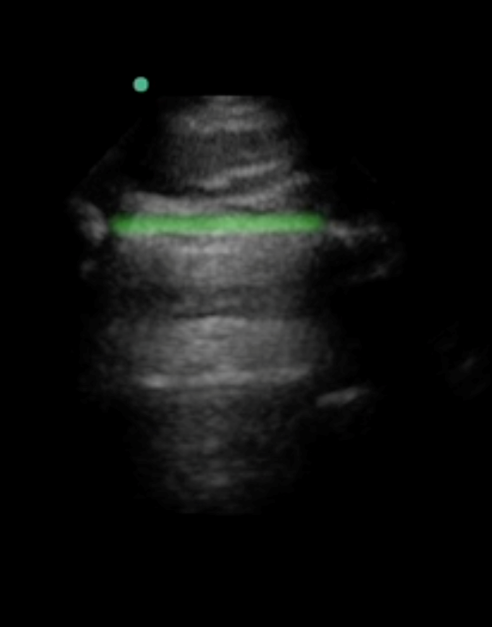

eFAST Pleural Line Highlighted 2 Image

Highlighted Area: Pleural Line